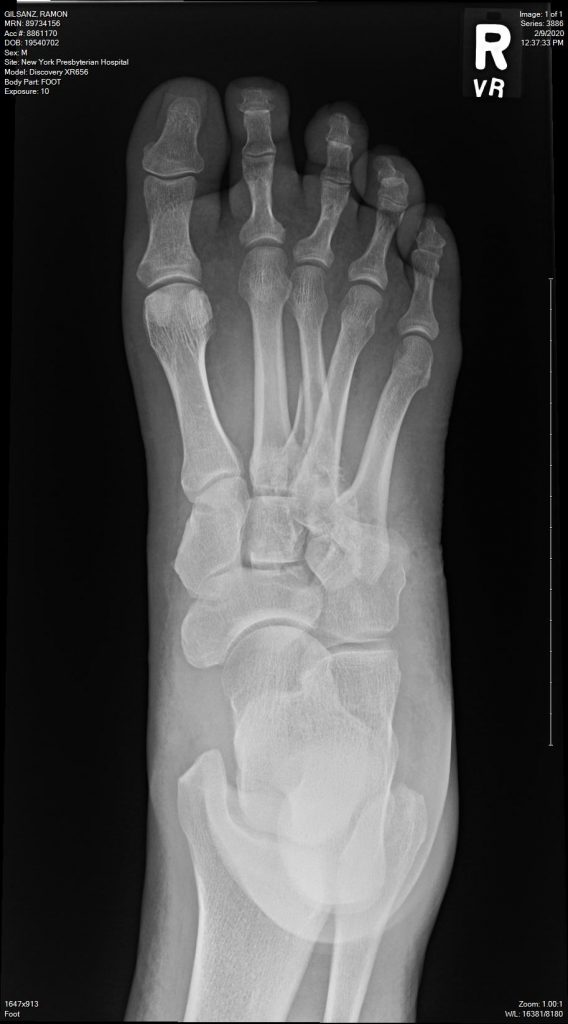

Last February I was in a devastating motorcycle accident. Four of the five bones that connect the ankle to the toes were broken, several in multiple places some of the broken bones punctured the skin in what is called an open or compound fracture. I was told by multiple doctors that I would never walk again. I made my way to Dr. Dziadosz (3 plane rides and 60 hours after the accident) with the help of family and friends. Dr. Dziadosz told me with confidence that I would walk again within the year. He was right. 11 months later I walk around 33 miles a week and I can do 8 miles in a day without a limp, and without a cane. Something I never thought would be possible again.